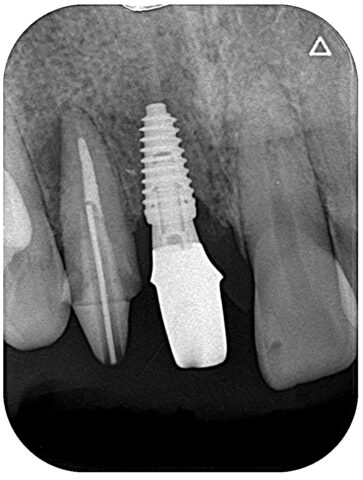

前歯インプラント

BEFORE

AFTER

症例情報

通院時の年齢

40代

性別

男性

通院目的

右上1の破折と右上2の審美障害

処置内容

右上1はインプラント補綴、右上2は補綴処置を行いました。

費用

約55万円

初診時

術中